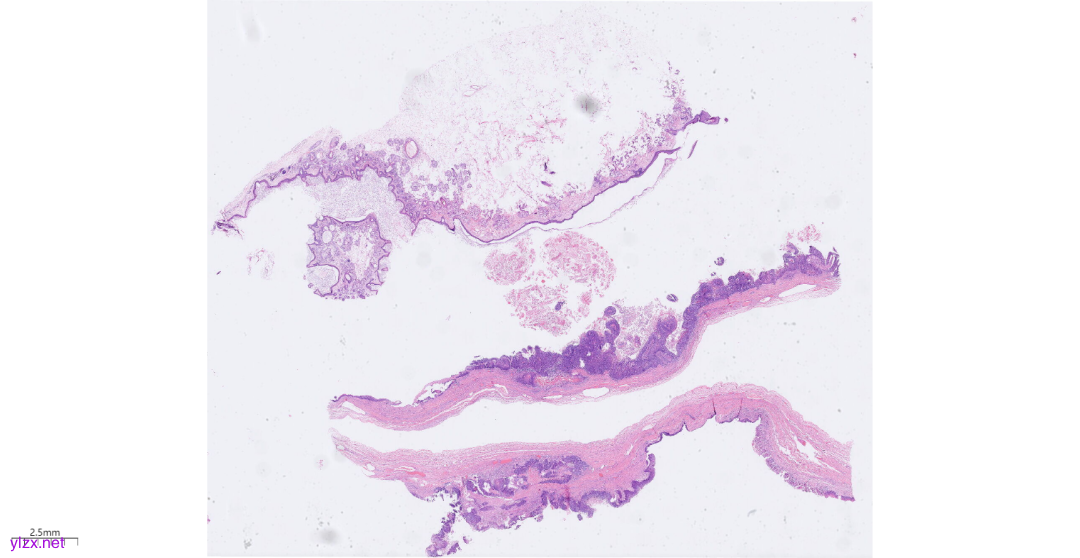

3.1大体肉眼观(图2):

灰白囊壁样组织,150×110×15mm,壁厚1-5mm,局部见头节,直径10mm,切面灰黄,质中,头节周围囊壁见大量乳头状菜花状凸起,直径1-9mm,切面灰白实性,质地脆,囊壁内见大量豆渣样物及毛发,附输卵管长40mm,管径8mm,伞端开放。

图2 大体肉眼观见卵巢囊壁见大量乳头状菜花状凸起,质地脆,囊壁内见豆渣样物及毛发。